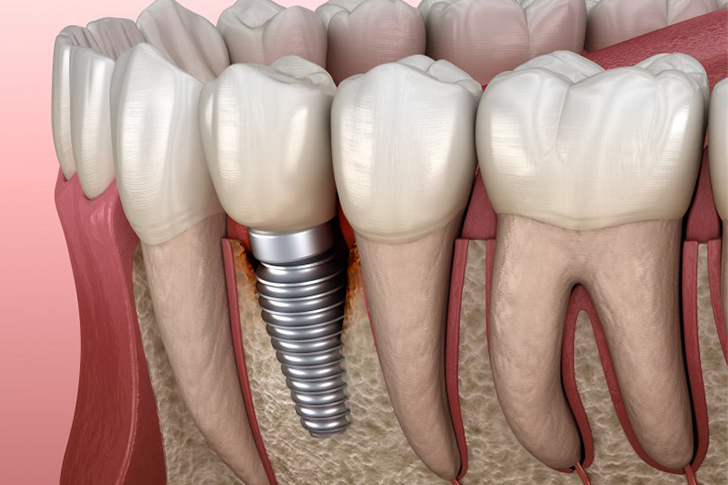

Dental implants are artificial tooth roots, typically made of titanium, implanted into the jawbone to support a replacement tooth or bridge. They provide a sturdy foundation, resembling natural teeth in both form and function.

Osseointegration is the process through which a dental implant anchors to the jawbone. This biological bonding is essential for the stability and longevity of the implant.

A comprehensive evaluation, including X-rays and dental impressions, is crucial to determine bone density and optimal implant placement.